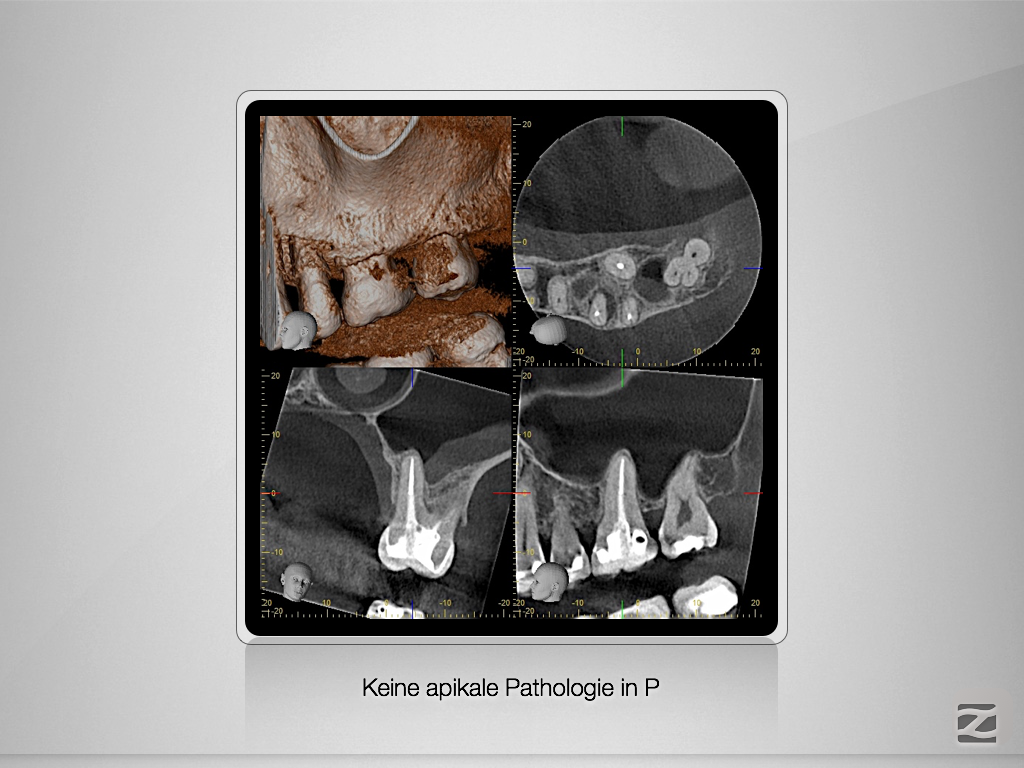

26D.004

X-Bein